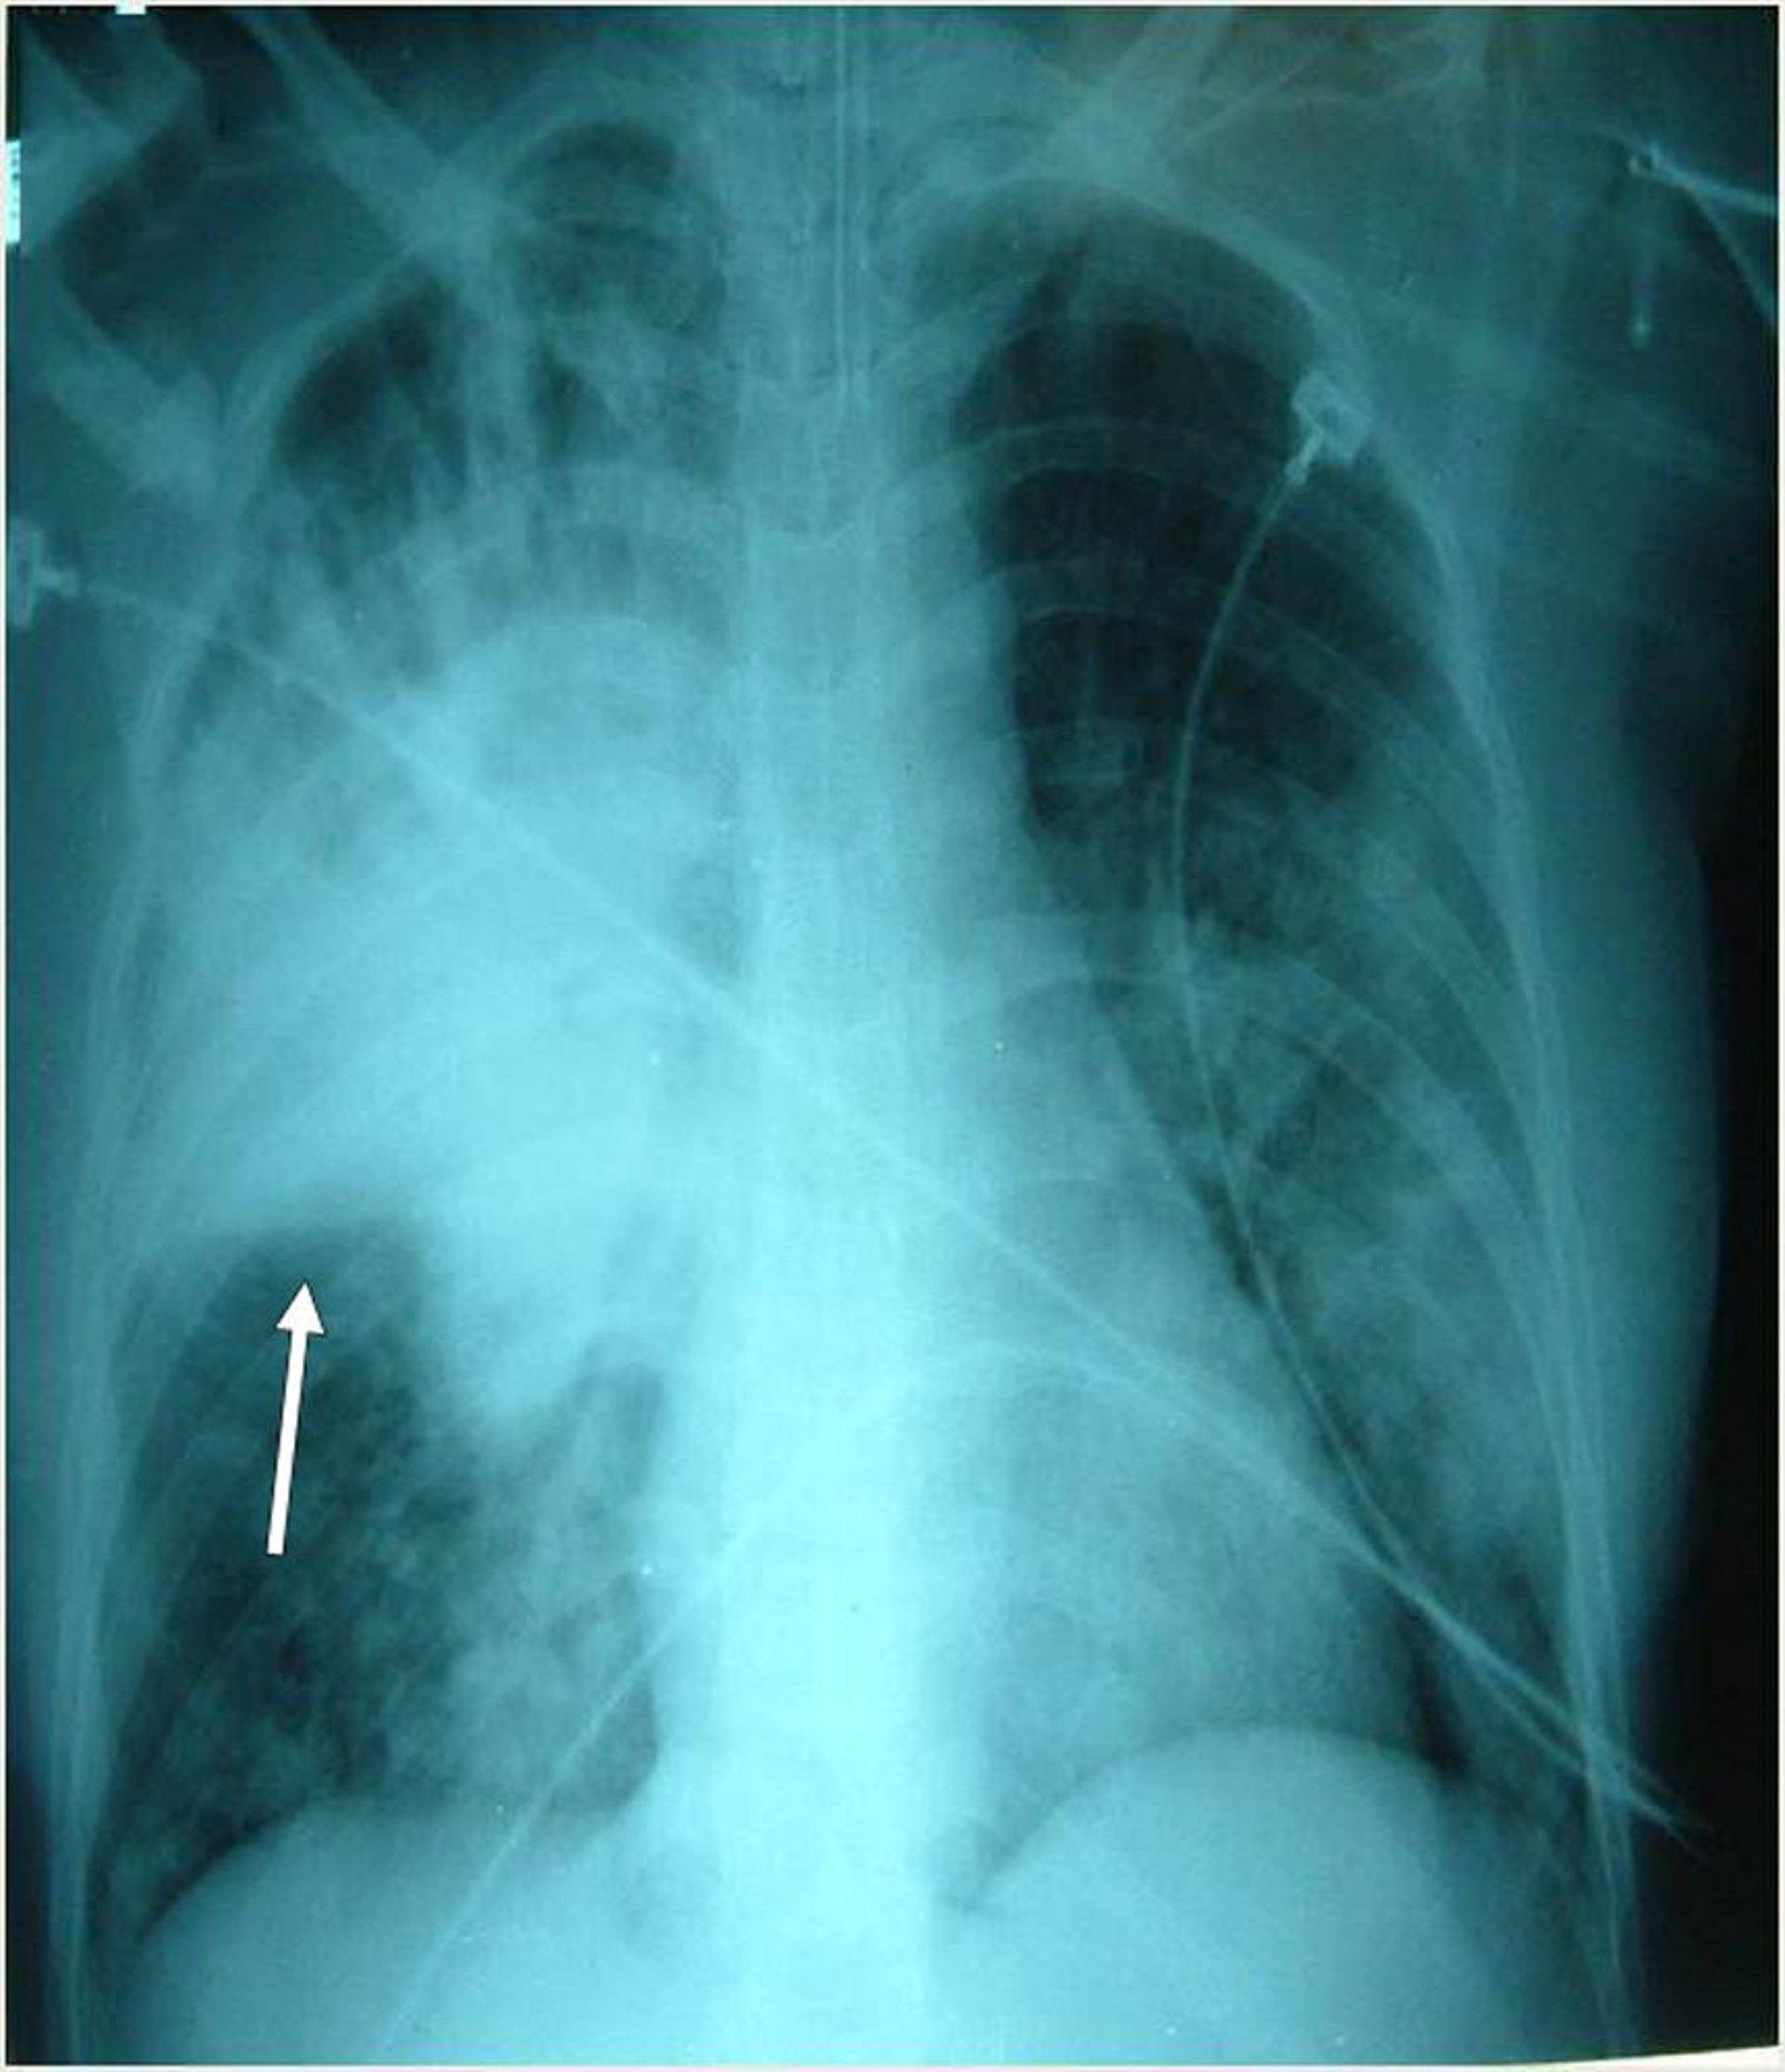

Тяжелая пневмония

У таких интубированных пациентов наблюдаются множественные двусторонние инфильтраты, наиболее заметные в правой верхней доле. Стрелка указывает на правую горизонтальную щель.

Photo courtesy of Thomas M. File, Jr., MD MSc MACP FIDSA FCCP.